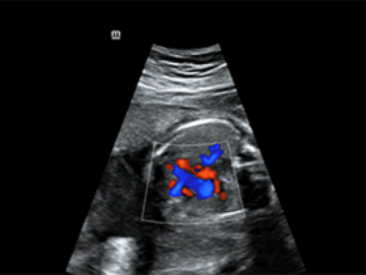

ImĂĄgenes clĂnicas